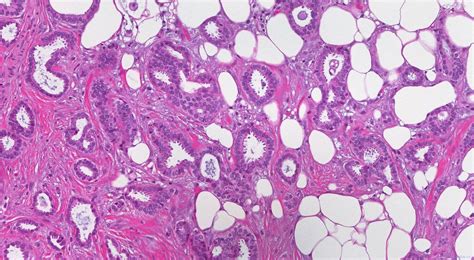

Invasive carcinoma of the left breast , also known as infiltrating carcinoma, is a type of breast cancer that has spread from its original location in the milk ducts or lobules into the surrounding breast tissue. This is in contrast to in situ carcinoma, which remains confined to its original location. Understanding the nuances of this condition is essential for accurate diagnosis, treatment planning, and, of course, proper coding using the International Classification of Diseases, Tenth Revision (ICD-10).

The diagnosis of invasive carcinoma typically involves a combination of physical exams, imaging studies (like mammograms, ultrasounds, and MRIs), and a biopsy. Once invasive carcinoma is confirmed, doctors will determine the stage and grade of the cancer. Staging refers to the extent of the cancer’s spread, while grading describes how abnormal the cancer cells look under a microscope. These factors play a crucial role in determining the best course of treatment, which may include surgery, radiation therapy, chemotherapy, hormone therapy, and targeted therapies.